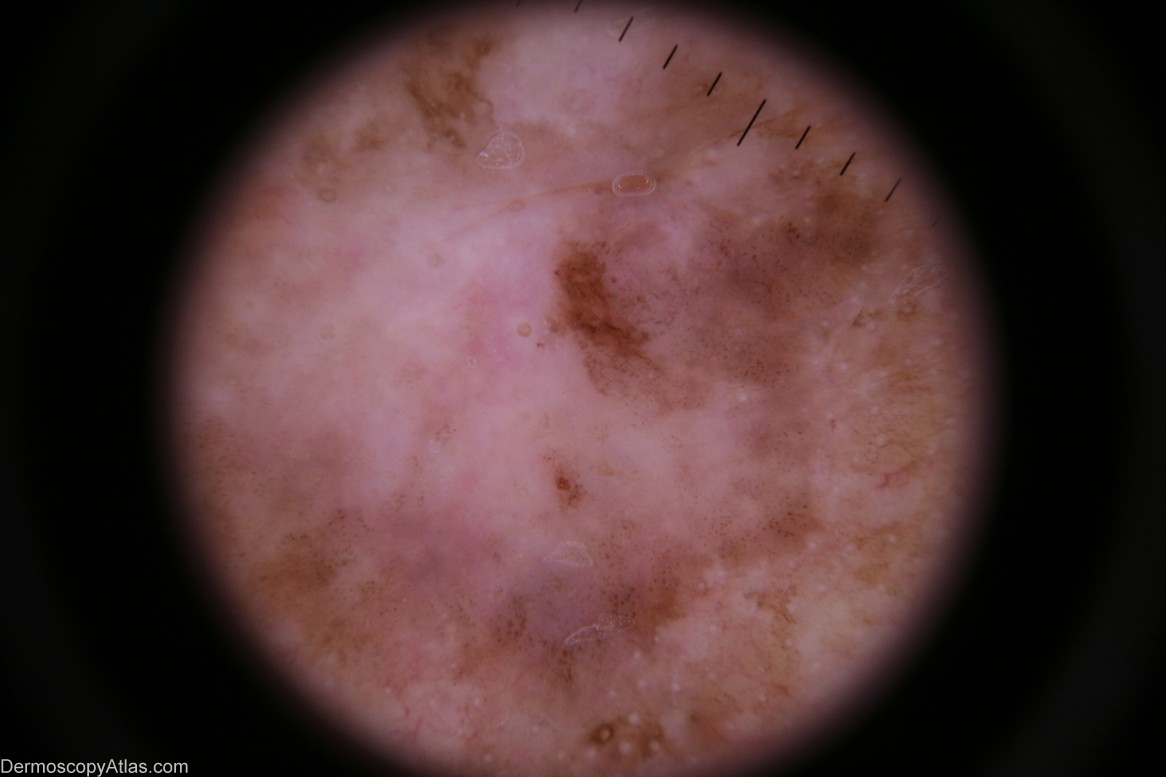

Description: Dermoscopy - There is no pigment network nor are there any other melanocytic features.The distribution of the pigment is asymmetrical. There are milky-red areas and aggregated brown dots. The white circular structures may be milia-like cysts in the adjacent seborrhoeic keratosis which was reported on histology.

History: This lesion was encountered at a routine skin check at the same time as a level 1 melanoma was discovered on his scalp (image 260 in this atlas). Shave biopsy was reported as "...pigmented intraepidermal carcinoma". The definitive excision was reported as "...pigmented intraepidermal carcinoma and seborrhoeic keratosis". IEC,s do sometimes arise in pre-existing seborrhoeic keratoses. This may be the case here or the two lesions may be separate and in collision. The skin on this man's back was severely sun-damaged.